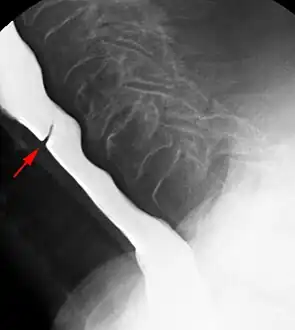

Esophageal web stenosis in barium swallow examination lateral view.

The diagnostic test of choice is a barium swallow.